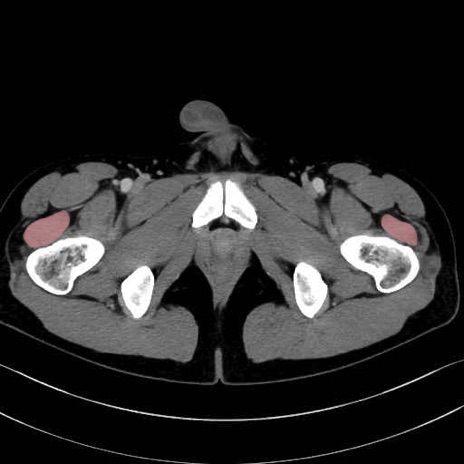

外側広筋(vastus lateralis) のCT画像の解剖

外側広筋 (Vastus lateralis)